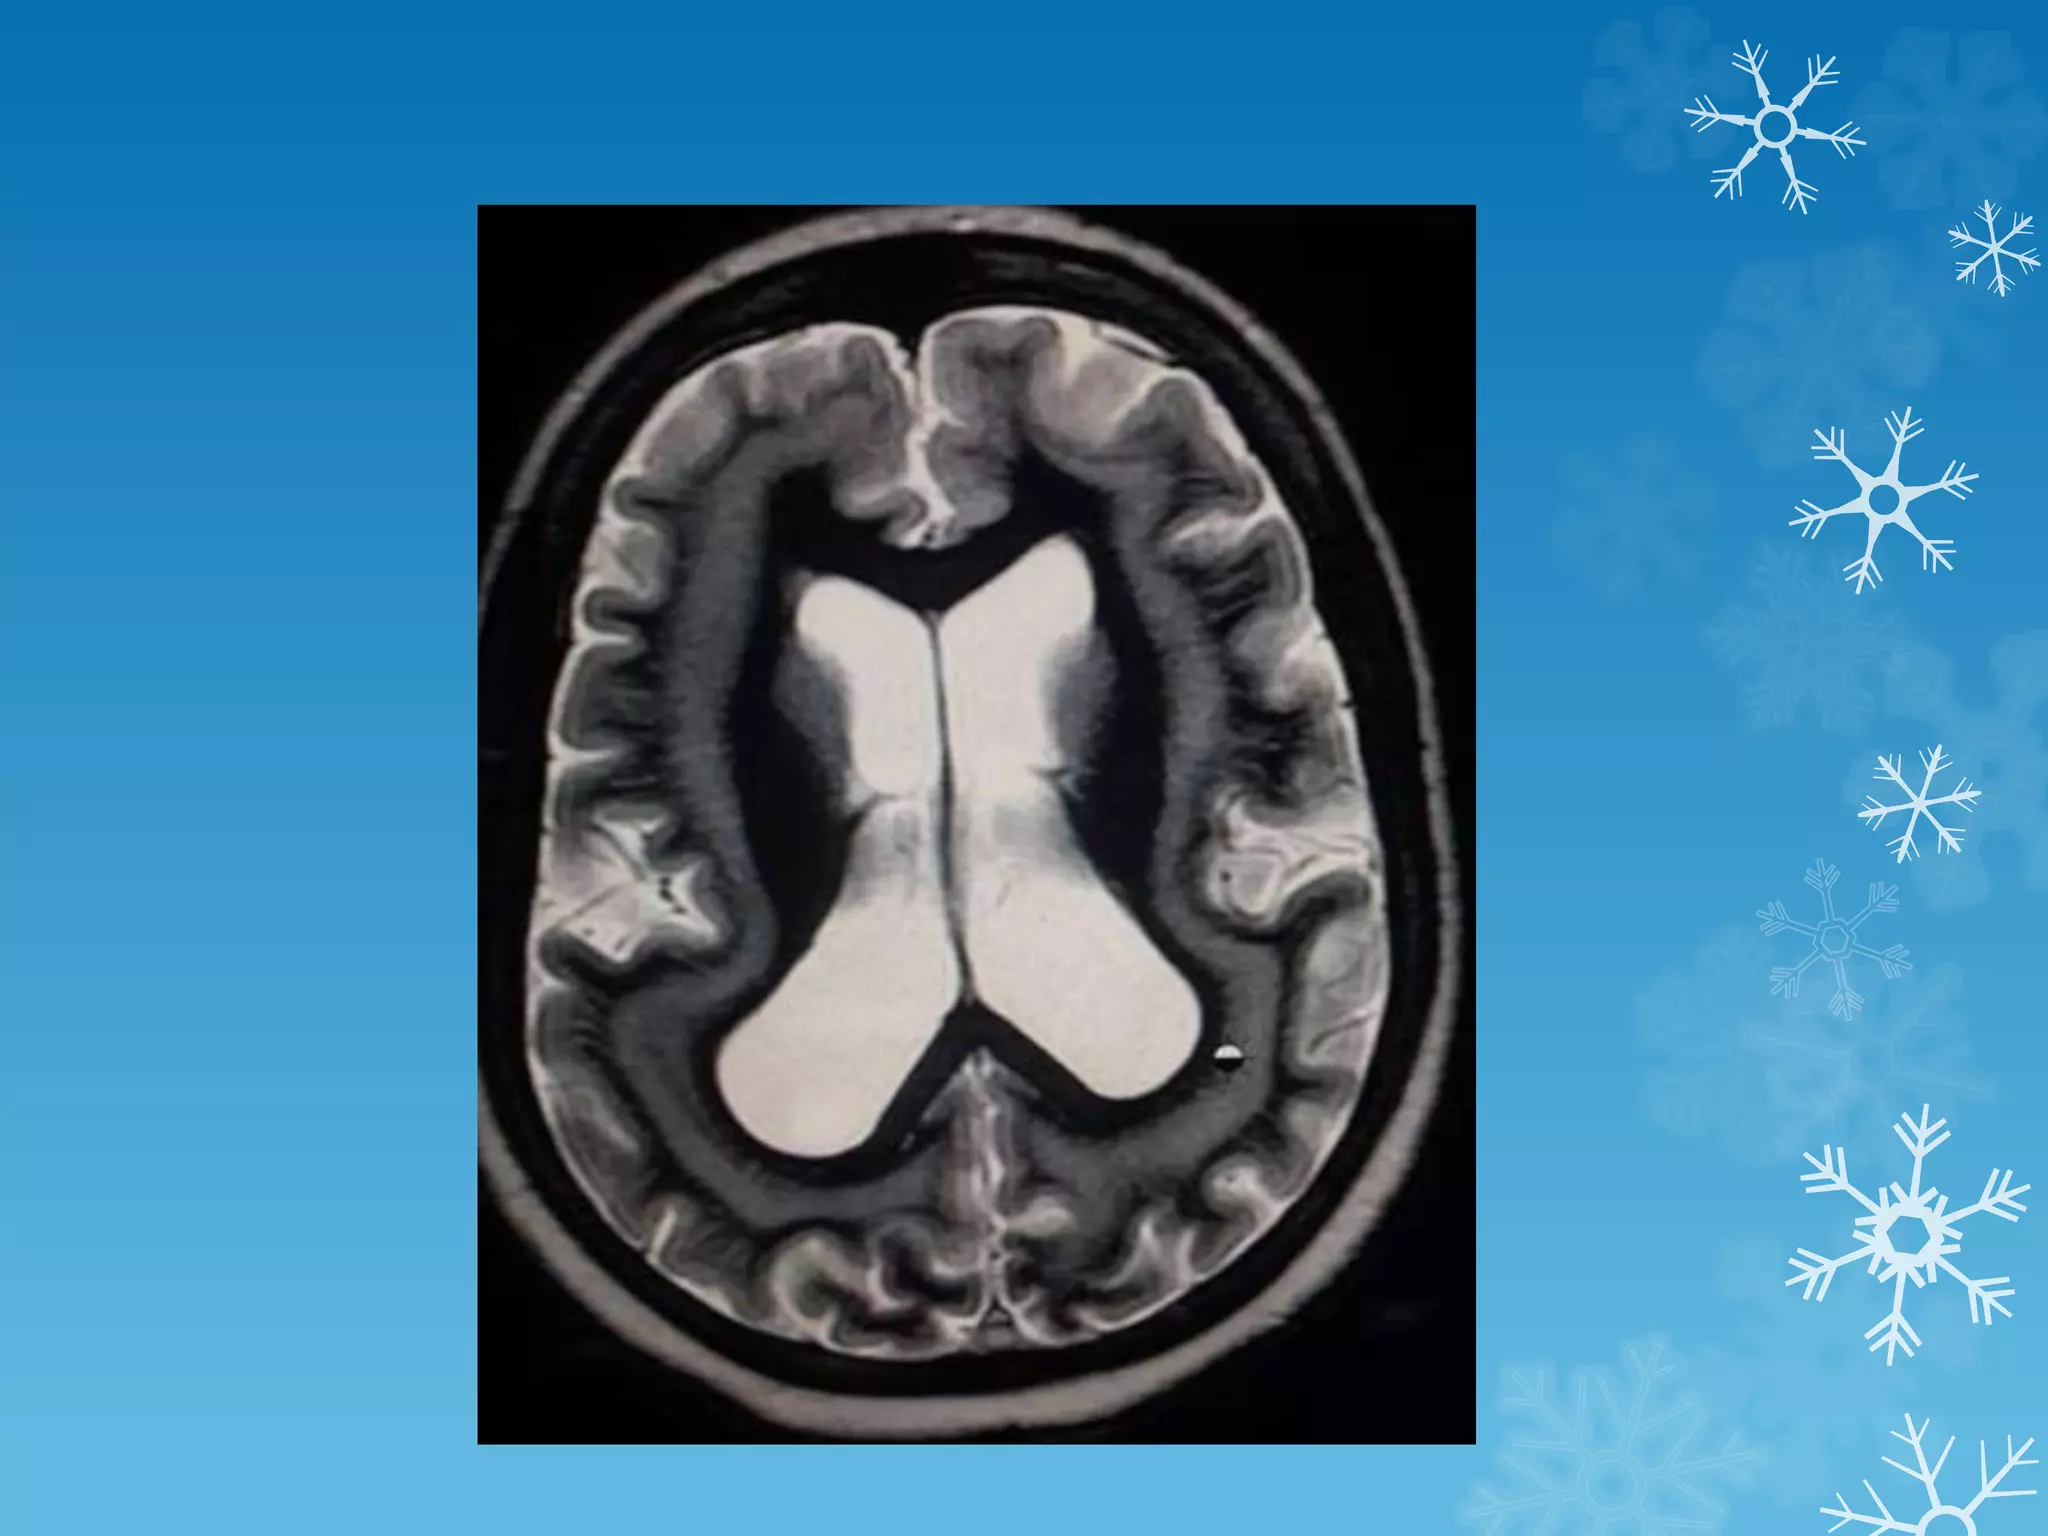

Band heterotopia